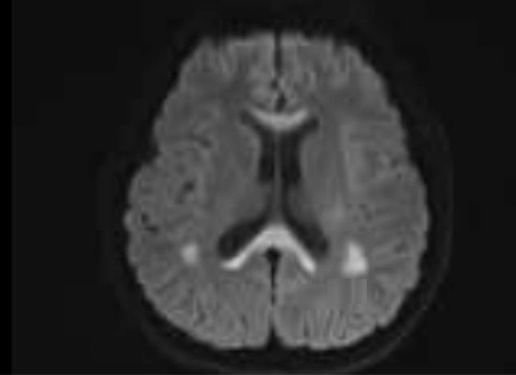

神经内科负责人张冲综合分析患者病史、体格检查、治疗后病情变化及头颅磁共振所示双侧对称性细胞毒性水肿异常信号,考虑患者诊断为可逆性胼胝体压部病变综合征(RESLES-2型)。治疗一周后小甘语言及吞咽功能恢复正常,复查头颅核磁共振可见小甘之前脑内对称性异常信号基本消失。

治疗后